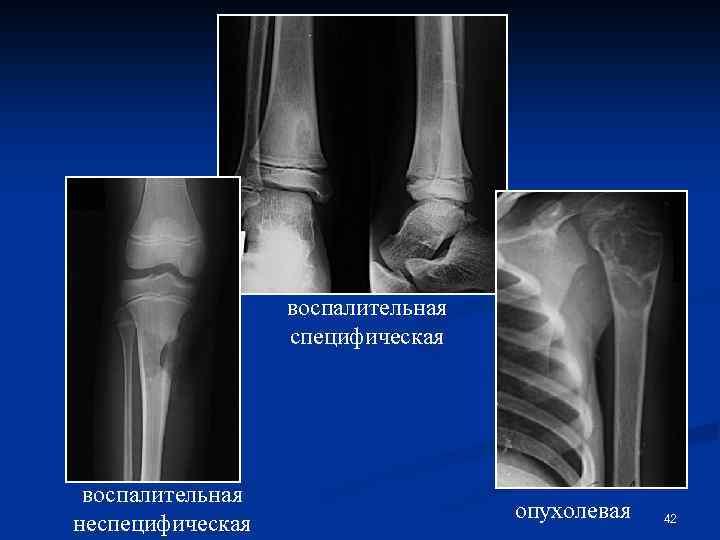

ДЕСТРУКЦИЯ – постепенно возникающее разрушение кости с замещением ее какой-либо другой патологической тканью Виды деструкции: Ø Ø Воспалительная деструкция § Неспецифическая (замещение кости гноем и воспалительными грануляциями) § Специфическая (замещение костной ткани специфической гранулемой – туберкулез, сифилис, бруцеллез, актиномикоз и др. ) Опухолевая деструкция Дегенеративно-дистрофическая д. (замещение фиброзной, фиброретикулярной или неполноценной остеоидной тканью) Деструкция от вытеснения 41

воспалительная специфическая воспалительная неспецифическая опухолевая 42